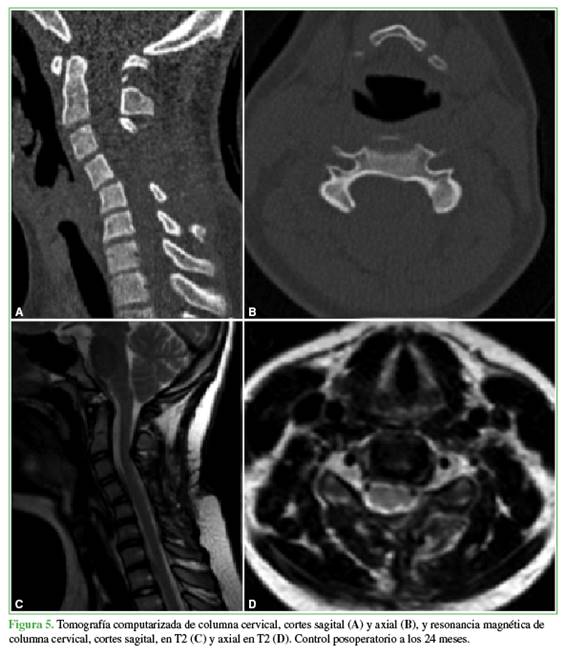

Niña de 11 años con diagnóstico de EMH que se atiende en el Servicio de Ortopedia Infantil desde 2010. Tiene múltiples lesiones en ambos brazos y piernas (Figura 1).

La paciente no tuvo complicaciones neurológicas y fue dada de alta al tercer día de la cirugía. Se mantuvo la inmovilización con un collar rígido durante 2 meses. El examen patológico confirmó el diagnóstico de osteocondroma. Tres meses después de la cirugía, desarrolló una cifosis local en el segmento C4-C5 que actualmente está en observación. A los 2 años de la intervención, no hay evidencia de recurrencia local en las imágenes de TC y RM (Figura 5).